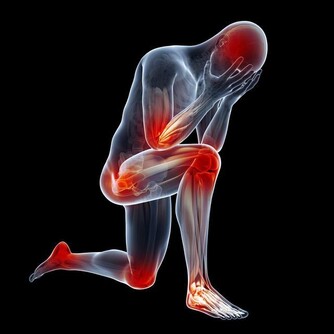

阿司匹林似乎是很多人都會放在醫藥箱中的居家常備藥物,它就像“萬能藥”一樣,不管是感冒發燒,還是關節風濕,阿司匹林都會派上用場,因為它是著名的止痛藥,而且是在藥店隨時都可以買到的非處方藥。不過我們需要注意的是,阿司匹林雖然應用廣泛,但是對於下面這些情況,不建議使用阿司匹林。